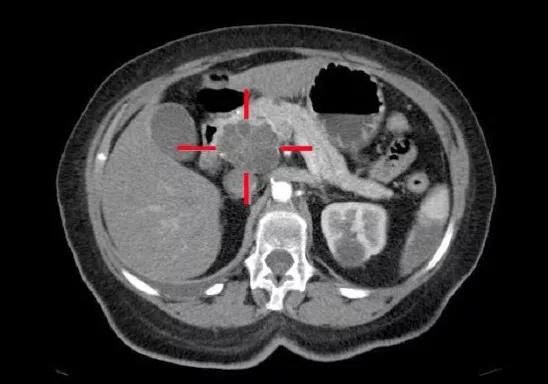

圖示胰腺癌影像掃描